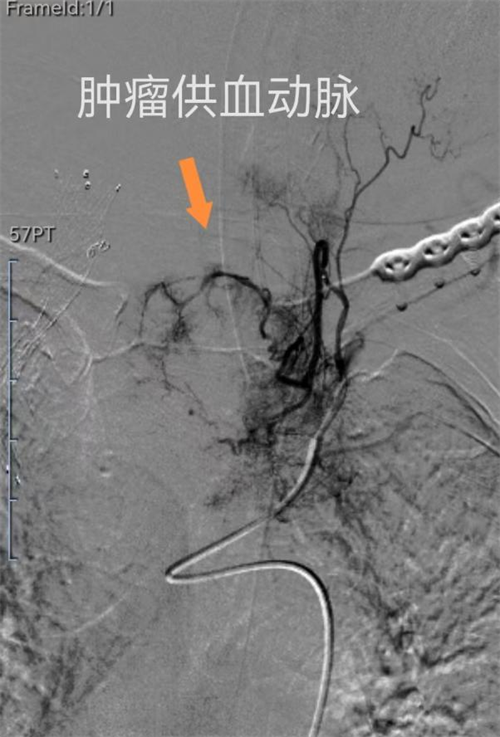

多科携手,为患者开启“生命之路”。手术由介入医学科和麻醉科协同完成。介入医学科副主任许泽兵带领介入团队在DSA机下精细操作,麻醉科全力保驾护航,手术有序推进,团队配合默契,无缝衔接。术中,先对肿瘤进行精准治疗(动脉灌注化疗栓塞),促使肿瘤坏死缩小;接着在右侧上腔静脉安置血管支架,解除肿瘤所致上腔静脉梗阻;最后在气管内安置气道支架,解除肿瘤所致气管梗阻,手术过程十分顺利。术后,李奶奶被转入重症医学科,经重症团队精心治疗,患者术后恢复良好。